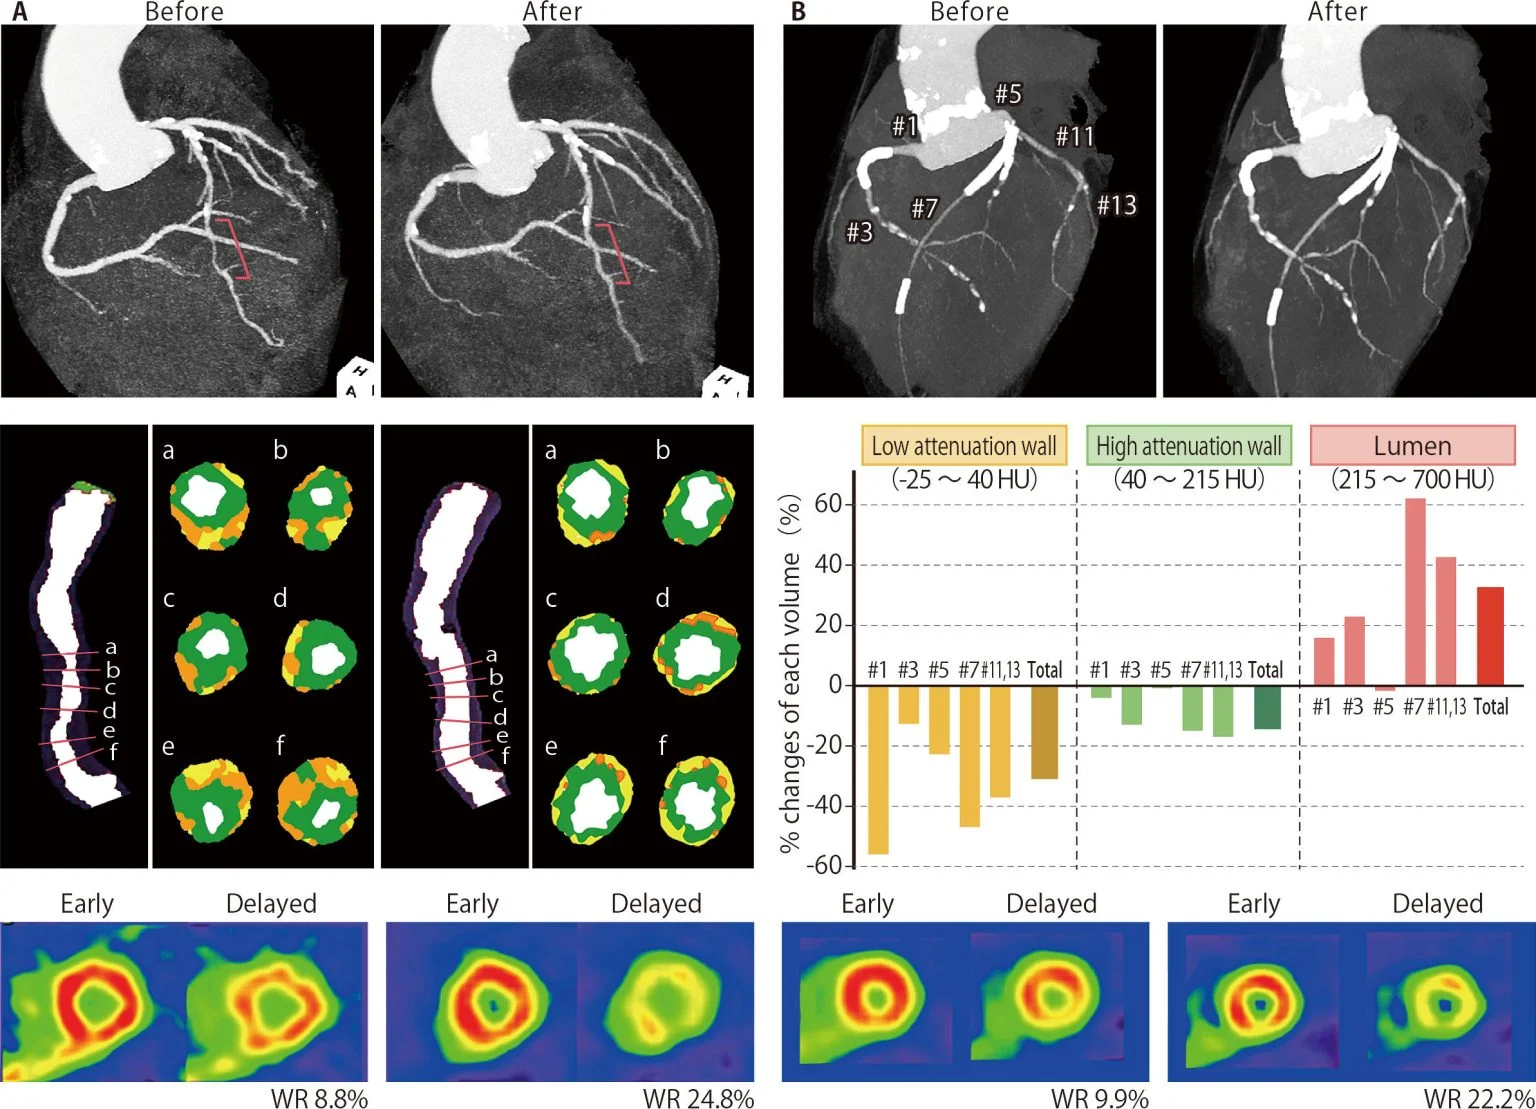

TGCV یا کاردیومیوواسکولاپاتی رسوب تریگلیسرید، یک اختلال نوظهور در سیستم قلبیعروقی است که با آترواسکلروز منتشر و باریک شدن عروق کرونری به دلیل رسوب تریگلیسرید شناخته میشود. این وضعیت ناشی از اختلال در تجزیه چربیها (لیپولیز) درون سلولهای عضلانی صاف عروق است و اغلب در بیمارانی دیده میشود که به درمانهای استاندارد پاسخ نمیدهند و معمولاً نیز تشخیص داده نمیشود. تصاویر A و B مربوط به دو بیمار در دهه شصت زندگی آنها هستند که از آنژین صدری مقاوم و دیابت قندی رنج میبردند. پس از تشخیص TGCV، هر دو بیمار مصرف مکمل غذایی تریکاپرین را آغاز کردند و علائم آنها ظرف چند ماه بهطور قابل توجهی کاهش یافت. تصویربرداری سیتیآنژیوگرافی کرونری در بررسیهای پیگیری، کاهش بارز ضایعات آترواسکلروتیک همراه با اتساع مجرای رگ را نشان داد (شریان کرونری چپ با خط قرمز در بالای تصویر A و شریانهای کرونری راست و چپ در بالای تصویر B). همچنین نواحی با تراکم پایین که از سمت خارجی رگ (آدونتیس) دیده میشدند (نواحی زرد و نارنجی در تصویر میانی A) و نیز حجم این نواحی (میلههای زرد در تصویر میانی B) کاهش یافتند که نشاندهنده کاهش مشارکت چربی در دیواره رگها است. این مشاهدات با افزایش لیپولیز میوکارد در اسکن ایزوتوپی با استفاده از ید-۱۲۳-بتا-متیل-پ-یودوفنیلپنتادکانوئیک اسید (پانلهای پایینی) همراه بود.

کنایچی هیراانو میگوید: «اکنون گزارش میدهیم که کاهش شگفتانگیز آترواسکلروز منتشر کرونر در دو بیمار مبتلا به TGCV مشاهده شده است؛ هر دو بیمار از درد قفسه سینه مقاوم و دیابت رنج میبردند تا اینکه به TGCV مبتلا شدند، و مصرف مکمل غذایی تریکاپرین منجر به کاهش علائم شد.»

تریکاپرین یک مکمل غذایی است که به تجزیه لیپیدها در سلولهای عضلانی قلب کمک میکند. علاوه بر کاهش علائم آزاردهنده و دردناک این بیماران، تریکاپرین باعث کاهش شگفتانگیز رسوبات تریگلیسرید در عروق قلب نیز شد.